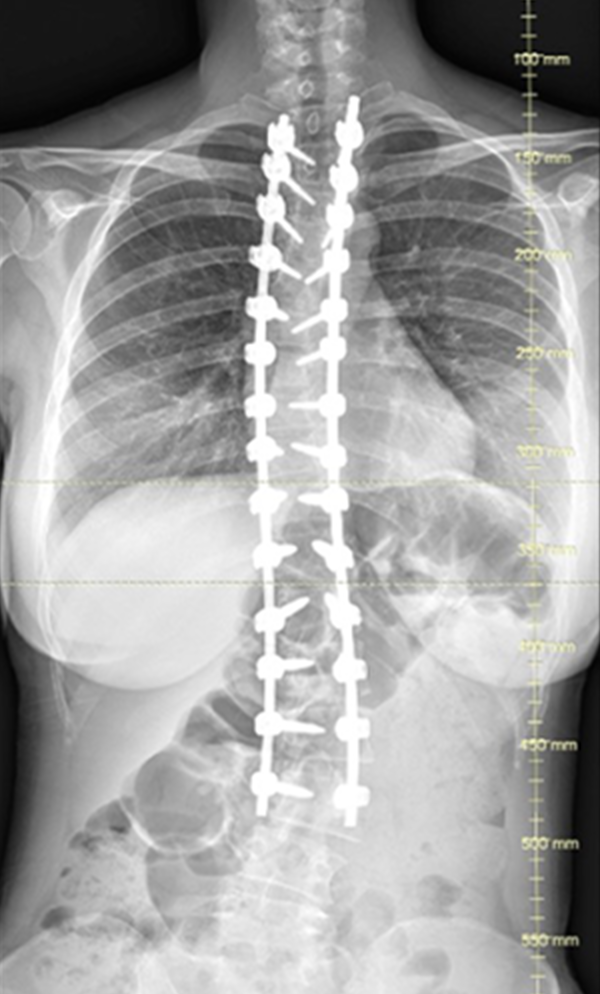

Gallery : Before - After